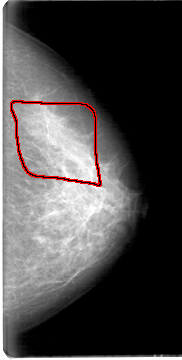

FILE: D_4052_1.LEFT_CC.OVERLAY

TOTAL_ABNORMALITIES 1

ABNORMALITY 1

LESION_TYPE CALCIFICATION TYPE AMORPHOUS DISTRIBUTION SEGMENTAL

ASSESSMENT 0

SUBTLETY 1

PATHOLOGY BENIGN

TOTAL_OUTLINES 1

BOUNDARY